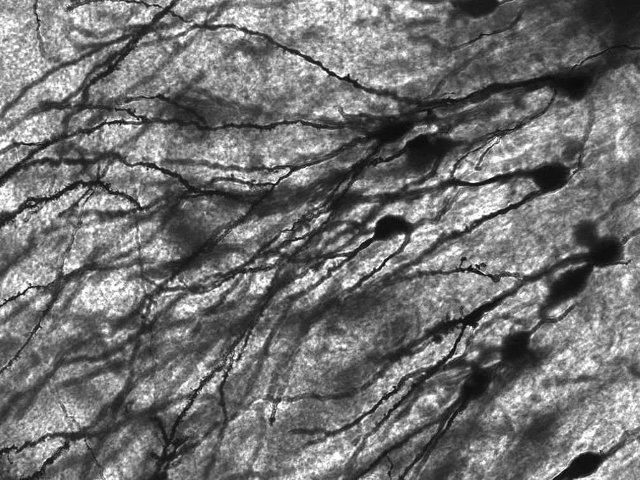

3. Οι άνθρωποι αναπτύσσουν συνεχώς εγκεφαλικά κύτταρα

Μέχρι τη δεκαετία του 1980 οι επιστήμονες πίστευαν ότι οι ενήλικες είχαν ένα συγκεκριμένο «ποσό» εγκεφαλικών κυττάρων.

Ο επιστήμονας Michael Kaplan βρήκε νευρικά πρόδρομα κύτταρα στον εγκέφαλο μιας ενήλικης μαϊμούς, υποδηλώνοντας ότι ο εγκέφαλός της υπέστη νευρογένεση, ή αλλιώς δημιουργία νευρώνων.

Το 2013 ερευνητές μπόρεσαν να προσδιορίσουν την ηλικία των κυττάρων του ιππόκαμπου από ανθρώπους που είχαν αποβιώσει. Τα κύτταρα που ήταν νεότερα από την ηλικία των αποθανόντων ήταν μια απόδειξη για το ότι ο εγκέφαλος όντως δημιουργεί τους δικούς του νευρώνες.